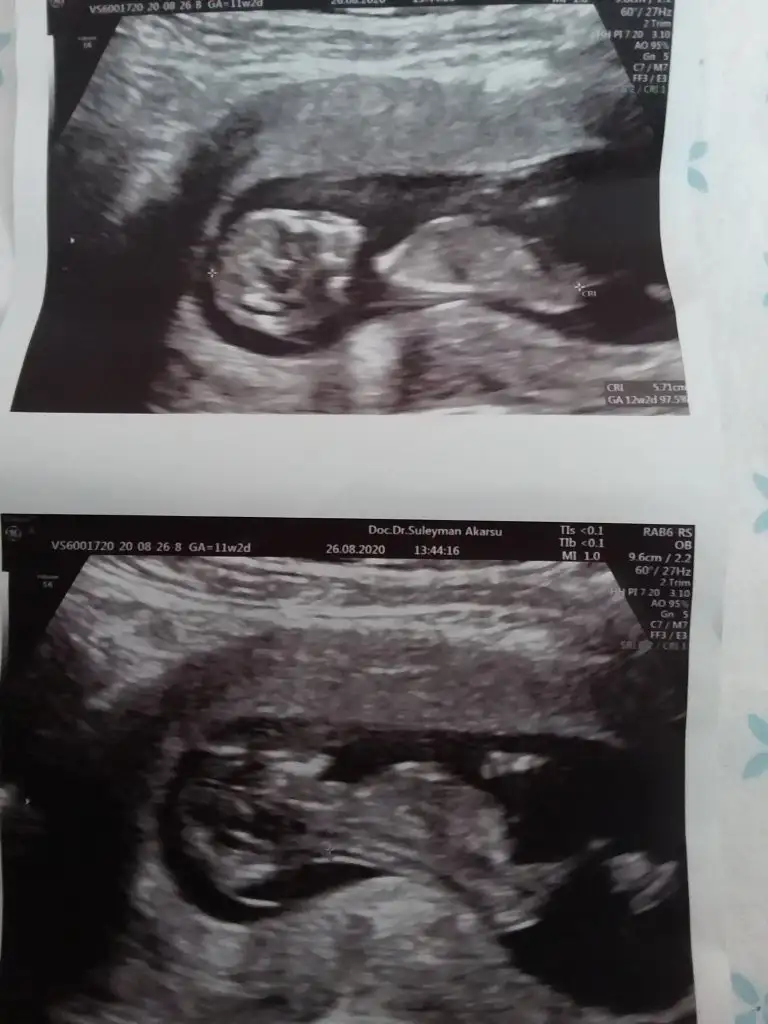

Erkek bebişMerhaba, 12. haftadan ultrason görüntülerimiz. Yorum yaparsanız çok sevinirim.Eki Görüntüle 2678844 Eki Görüntüle 2678845 Eki Görüntüle 2678846 Eki Görüntüle 2678844 Eki Görüntüle 2678845 Eki Görüntüle 2678846 Eki Görüntüle 2678844 Eki Görüntüle 2678845 Eki Görüntüle 2678846 Eki Görüntüle 2678846 Eki Görüntüle 2678844 Eki Görüntüle 2678845 Eki Görüntüle 2678846 Eki Görüntüle 2678844 Eki Görüntüle 2678845 Eki Görüntüle 2678846

Bana da öyle geldi bi de erkek olsa belli olurdu bu hafta dedi cogu kisi. Kız daha geç görünüyormuş bakalım ne cikacak iki hafta sonra yazarımKız gibi sanki